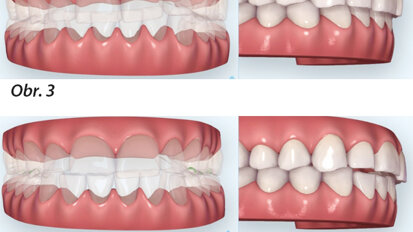

Hybridní terapie alignery